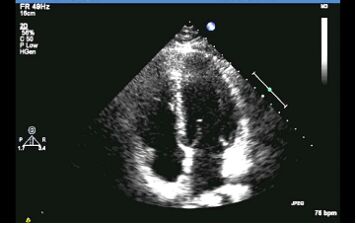

32.關於下圖心臟超音波的敘述,下列何者錯誤? (A)此張超音波可辨認出左心房、左心室以及右心房、右心室(B)此張心臟超音波為心尖四腔室圖(C)此張超音波可診斷中度二尖瓣逆流(D)此張超音波可看到二尖瓣與三尖瓣